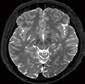

2. Vergleich eines cranialen CTs mit und ohne Deep Learning Rekonstruktion AiCE:

CCT AiCE

„AiCE unterstützt die Diagnosefindung in der Neuroradiologie dank der sofort sichtbar besseren Bildqualität bei gleicher Dosis.“